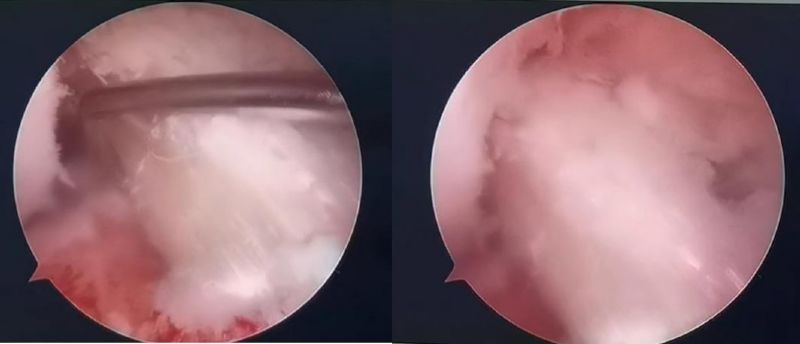

經(jīng)患者同意后,李鵬主任手術團隊制定詳細手術方案。手術如期進行,經(jīng)團隊密切配合,對幾位患者分別順利完成關節(jié)鏡下膝關節(jié)鏡鏡檢、關節(jié)清理、股薄肌半腱肌取腱移植術、前交叉韌帶重建術、軟骨損傷微骨折術、半月板縫合修整術等。

鏡下重建前交叉韌帶走形、張力良好

我院骨關節(jié)鏡手術創(chuàng)傷小、恢復快,幾位患者分別于術后5-7天好轉出院?;颊哂H身感受膝關節(jié)快速康復過程,對科室醫(yī)護表示感激,對早日回歸正常的生活、工作及運動狀態(tài)充滿信心。